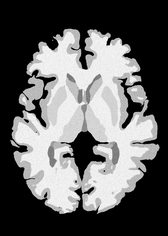

4.2 Registration to a 100 micron ex-vivo brain MRI volume

To showcase the efficacy of our method on real large scale images, we register a 250 in-vivo MRI image (Lüsebrink et al., 2017) to a 100 ex-vivo FLASH human brain volume (Edlow et al., 2019). This represents an inverse problem with more than 11.2B optimizable parameters (compared to 20M for clinical datasets), or 44.8GB of GPU memory. The entire problem does not fit on most GPUs, necessitating distributed multimodal registration. We optimize a composite transform - affine followed by a diffeomorphic mapping; details can be found in Section E.1. Multimodal deformable registration took 58 seconds on 8 NVIDIA A6000 GPUs, which is unprecedented at this resolution. Fig. 6 shows qualitative results, highlighting the ability to register highly detailed structures such as cerebellar white matter; these structures are not visible at macroscopic scales. The resultant advantages of performing registration at this scale can allow researchers to characterize the neuroanatomy at microscopic resolutions and allow morphometric analysis of cortical layers and subcortical nuclei among other structures.